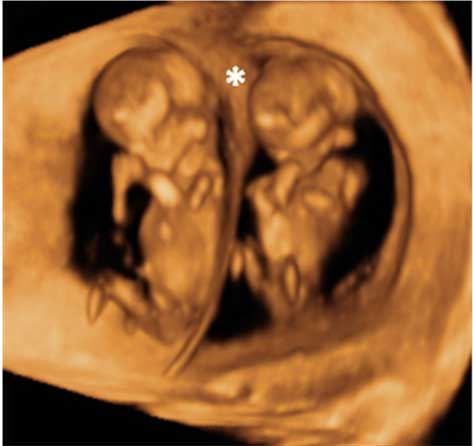

Así se ve un feto de 12 semanas de embarazo en una ecografía en 2D y en un ultrasonidos en 3D. En ambas se distingue los brazos y las piernas.

Podemos ver el bebé de 12 semanas de gestación en una imagen de dos dimensiones (a la izquierda, tumbado) y en tres dimensiones (a la derecha y en posición vertical). Las extremidades del feto (brazos y piernas) son visibles en ambos exámenes ecográficos.